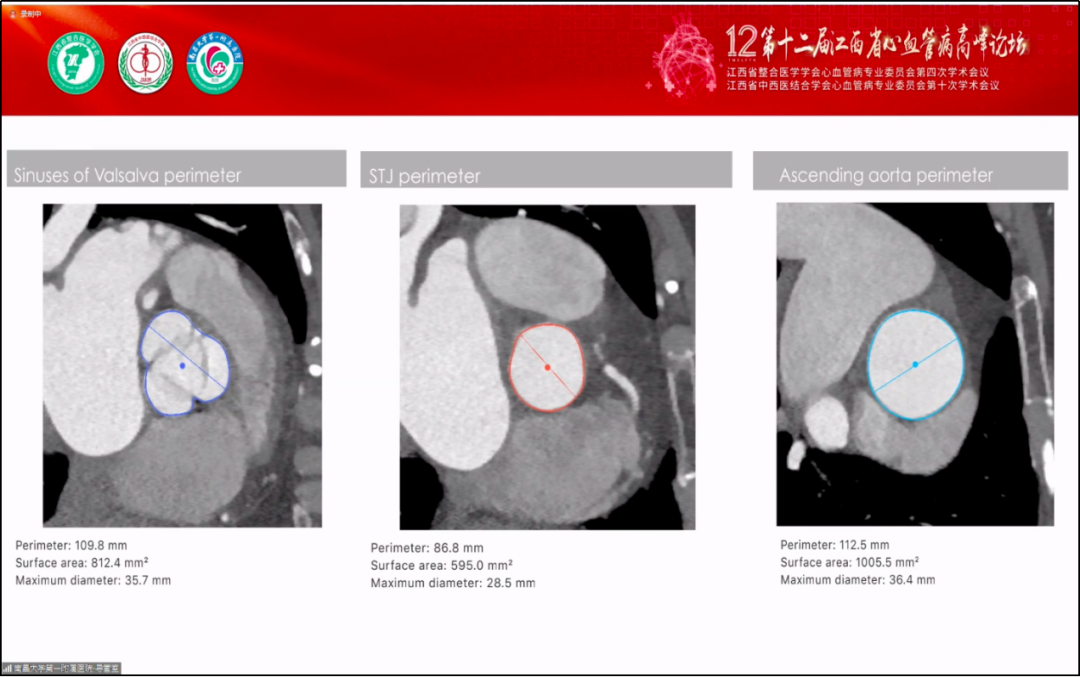

术前CT结果显示,主动脉瓣呈三叶瓣,重度关闭不全,瓣环周长75.9mm,平均直径24mm;LVOT周长79.4mm,平均直径25mm;升主动脉周长112.5 mm;STJ周长86.8mm;左冠开口高度12.4mm、右冠开口高度16.9mm。

术前CT重建结果